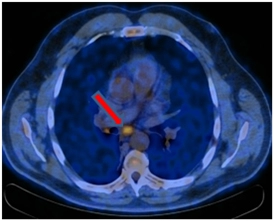

ПЭТ-КТ от 12.01.2017. В правом легком определяется мягкотканое образование метаболическим размером 30×24 мм с кальцинатом в структуре SUVmax=21,36, перекрывающий просвет промежуточного бронха справа сразу за уровнем ответвления среднедолевого бронха с формированием картины «культи бронха» – в бифуркационном лимфатическом узле до 20 мм SUVmax=4,77.